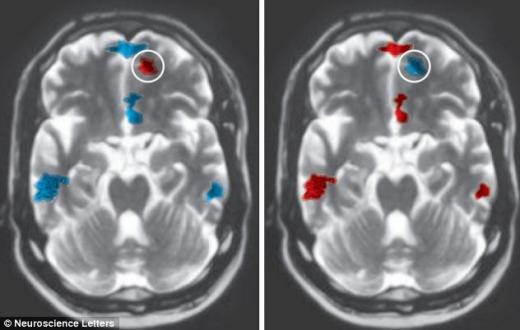

공개된 사진은 좌측이 3년 이상 사귄 사람, 우측이 그렇지 못한 이의 뇌스캔 이미지다. 붉은색으로 나타난 부분이 활발한 움직임을 보이는 곳이며 푸른색은 그 반대를 나타낸다.

그 결과, 만남을 지속한 참가자는 그렇지 못한 이보다 시각적인 아름다움에 대해 감정적인 반응을 보이는 꼬리핵(미상핵) 부분이 활동적이지만 비판과 판단에 연관된 안와전두피질은 비활동적인 것으로 나타났다.

또한 만남을 지속한 연인의 뇌는 쾌감 중추가 덜 활동적인 것으로 확인됐다. 무언가에 중독되거나 보상을 원하는 이런 영역이 비활성화되는 것은 포만 및 만족과 연관돼 있다고 과학자들은 말한다.